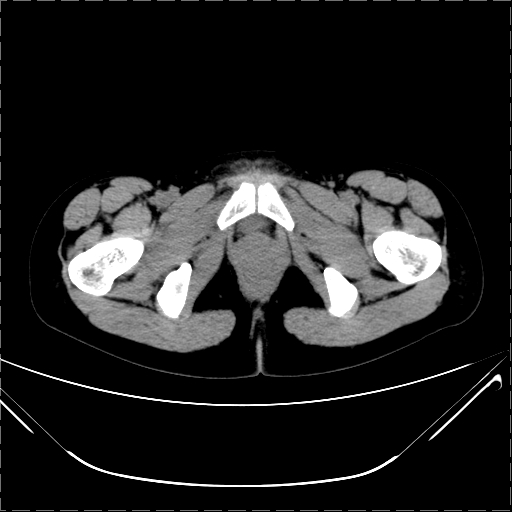

女 29岁 突然腹部疼痛1天 b超示子宫左后方肿块。月经正常。

请各位指教 该病人子宫周围云絮状高密度影是什么

影像表现复杂,膀胱上见一囊性包块,比膀胱密度高,其内有不均匀稍高密度,似与道格拉斯窝肿物无分界,病灶没有张力,因其腹平坦,推定其具有流动性,但又似见包膜,而b超没有报告这一现象。确实没见过。考虑卵巢囊肿蒂扭转并囊内出血可能。

病变主要位于道格拉斯窝,而且大体形态比较扁平且贴合子宫直肠,无明显张力及对周围脏器压迫,所以考虑为液体,而中间可见囊样病变伴环形强化,期内还可见分隔影,结合突发急性腹痛故多考虑囊腺瘤伴破裂出血。

腹腔镜术后 卵巢黄体囊肿破裂出血